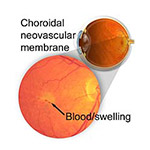

Choroidal Neovascular Membrane

A problem that is related to a wide variety of retinal diseases,